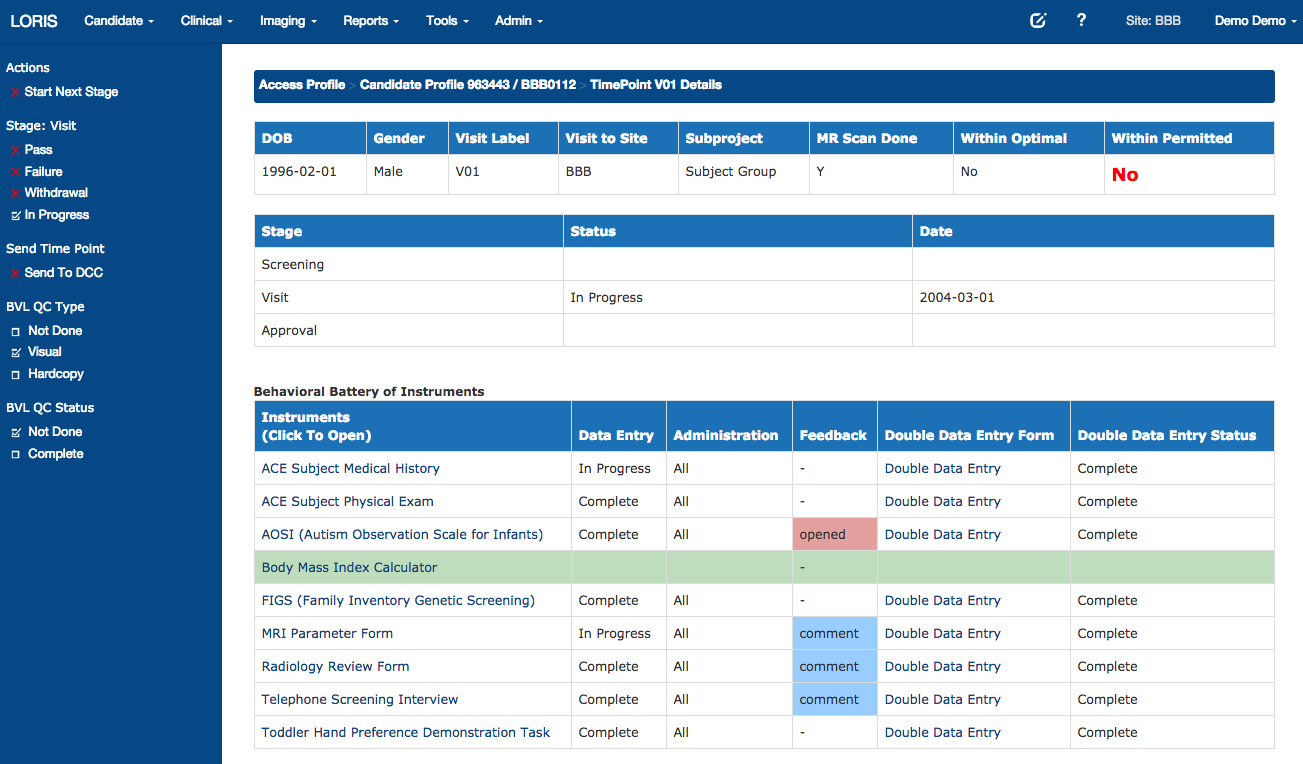

Timepoints

Battery of Measures

For list of 400+ instruments: https://sites.google.com/site/lorisinstrumentlist

Psychometric Data Entry